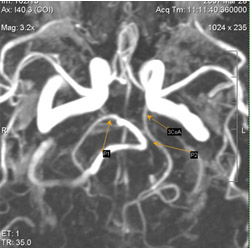

Задняя неполная трифуркация вса